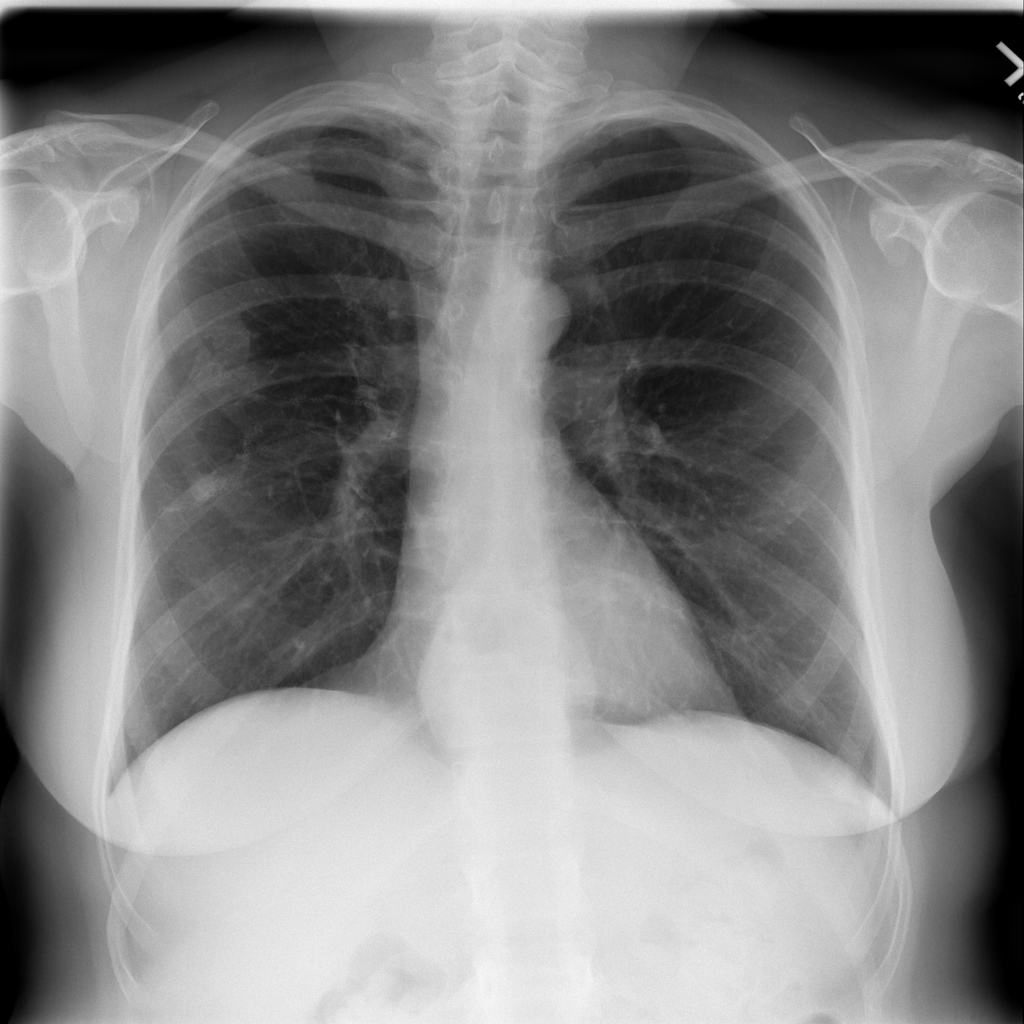

PAT-0ABD · IMG-000Hernia

PAT-0ABD · IMG-000

PA